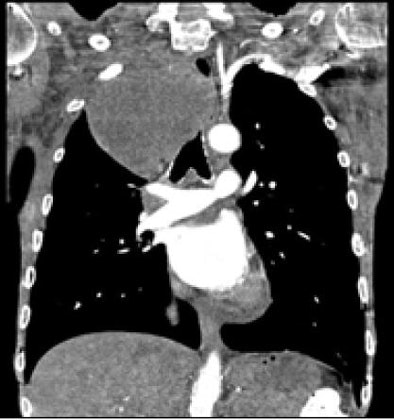

![]() |

| In a comparison of 70 patients scanned at pitch 2 versus 70 at pitch 3, acquisition times and doses were lower at pitch 3. Image quality did not differ significantly between the two techniques, but objective noise was slightly higher using the pitch 3 protocol. Data from Tacelli, Rémy-Jardin et al, RNSA 2008. |